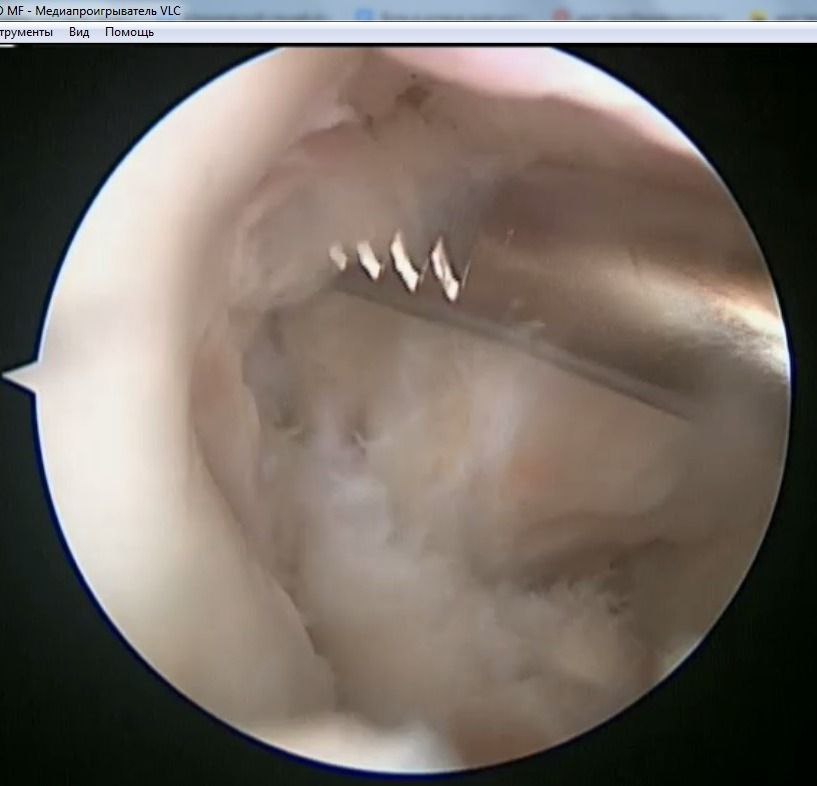

Наложения артроскопического шва заднего рога медиального мениска

По итогам исследования и определения диагноза пациенту был предложен и реализован план лечения: предоперационная реабилитация и проведение операции по поводу наложения артроскопического шва заднего рога медиального мениска, а также проведена пластика передней крестообразной связки сухожилием полусухожильной и тонкой мышц правого коленного сустава.